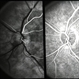

- Fundus fluorescein angiogram of a patient with arteritic anterior ischemic optic neuropathy and choroidal ischemia associated with giant cell arteritis.